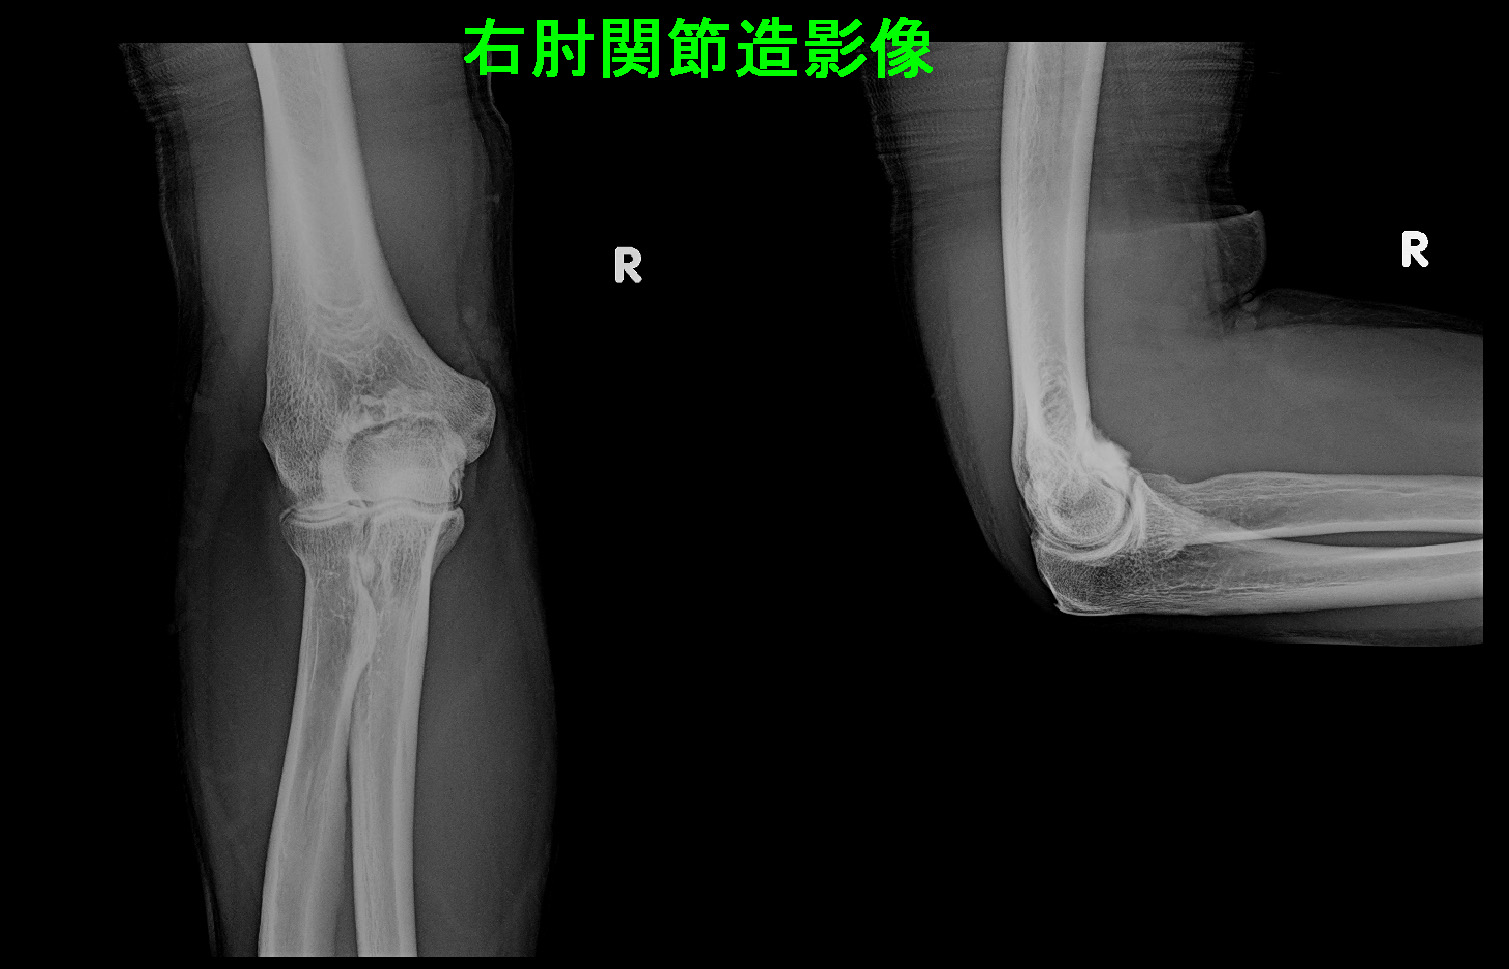

38才男 関節造影.jpg

関節内注射の造影像となります。以後、患者さんは受診されなかったため、6月13日(受診2か月後)に電話で症状の経過を確認しています。

注射の翌日より、VAS4~6の左肘痛はVAS2に軽減したそうです。6月に入ってVAS3~4となっているということでした。